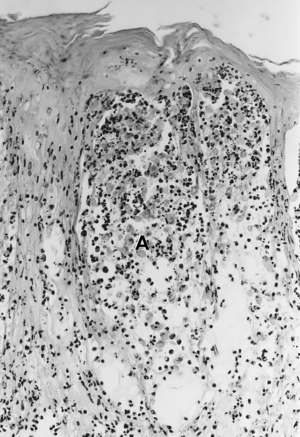

Foot-and-mouth disease - acantholysis in a sample of a skin vesicle: Necrosis of the stratum spinosum can be observed, and keratinocytes floating in the vesicular fluid (spongiosa). | |

Acantholysis is the loss of intercellular connections, such as desmosomes, resulting in loss of cohesion between keratinocytes,[1] seen in diseases such as pemphigus vulgaris.[2] It is absent in bullous pemphigoid, making it useful for differential diagnosis.

This histological feature is also seen in herpes simplex infections (HSV 1 and 2) and varicella zoster infections (chicken pox and shingles).